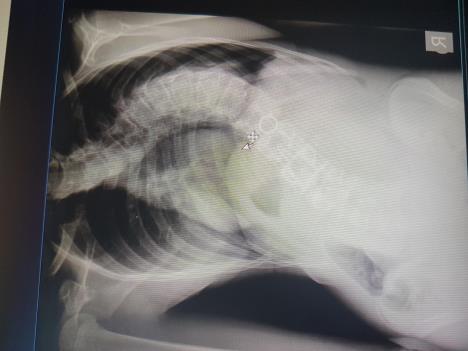

- Ministarstvo zdravlja takođe podržava projekat. Profesor Ventura je bio na prijemu kod ministra Lončara, koji je i lično došao da gleda operaciju skolioze u KC Kragujevac - kaže dr Vlajović, naglašavajući da “ovaj projekt ima značajan aspekt uštede za državu”. I sami smo svedoci raznoraznih akcija prikupljanja pomoći preko sms poruka za lečenje dece, i kontraverzi koje one izazivaju.

- Prošle godine smo operisali dečaka ѕa koga su sredstva bila sakupljana putem sms-a na lečenje u Italiju, a za čiju je operaciju bilo potrebno skupiti oko 180.000 eura. Kod nas, u KC Kragujevcu, operacija je koštala samo neophodni ugradni materijal oko 15.000 eura. Osim što deci obezbeđujemo lečenje od strane najpoznatijih hirurga čini se velika ušteda i za roditelje, i za zdravstveni fond, a deci omogućavamo oporavak i lečenje u poznatom okruženju. Procenjuje se da je ušteda za državu prosečno oko 100 hiljada eura po svakoj operaciji. Mada smo svedoci da je u više navrata, pojedini specifični materijal donirali i kolege lekari iz Španije-priča dr Vlajović o iskustvima u dosadašnjem razvoju projekta.